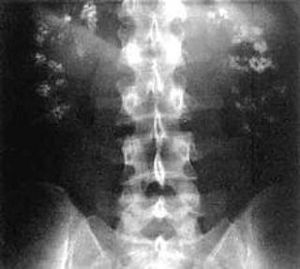

RTA is a condition results from a net decrease in tubular hydrogen secretion or bicarbonate reabsorption which produces a non-ion gap metabolic acidosis. There are three main types distal, proximal, and hyperkalmic. This abdominal radiograph shows bilateral nephrocalcinosis in a case of renal tubular acidosis.